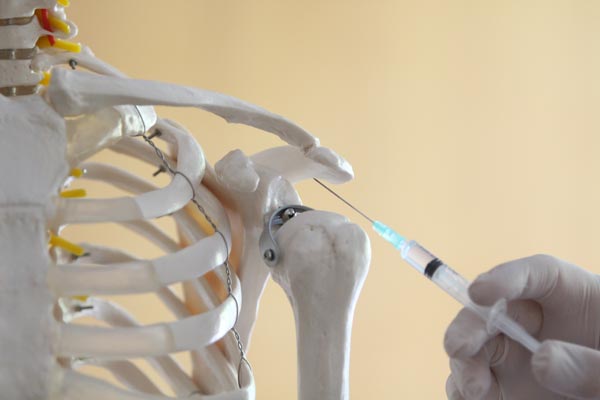

Tetiva m.supraspinatusa najčešći je uzrok boli. Slijede je jos dvije tetive rotatorne manžete, a svaka daje posebne simptome i posebne smetnje za pacijenta. Netko nemože podići ruku bočno, netko ne može uraditi unutarnju ili vanjsku rotaciju. Na pregledu je to jako lagano diferencirati, te započeti s tretmanima. Tretmani za tendinitise su transvezalne frikcije upalnih mjesta. Vidljivo na slici ispod. Ukoliko one ne pomognu, može se raditi infiltracija kortikosteroida u bolnu tetivu. Iza injekcije potreban je određeni period mirovanja I poštede ruke.

Slika 2 prikazuje transverzalnu frikciju tetive supraspinatusa